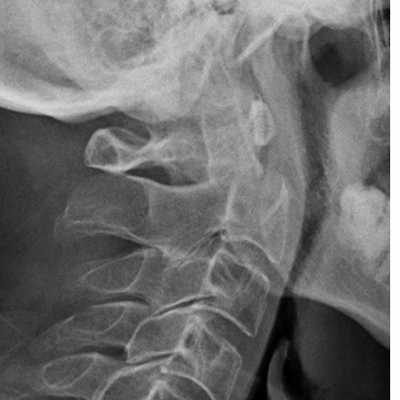

Перелом С2. Рентгенограмма в боковой проекции. Кольцо незамкнуто вследствие смещения зубовидного отростка назад.

Перелом С2 «повешенного». Рентгенограмма в боковой проекции. Смещение тела С2 вперед, отрыв задних элементов.

Обследование начинается со стандартной рентгенографии в 3 проекциях - боковой, передне-задней (прямой) и через рот.